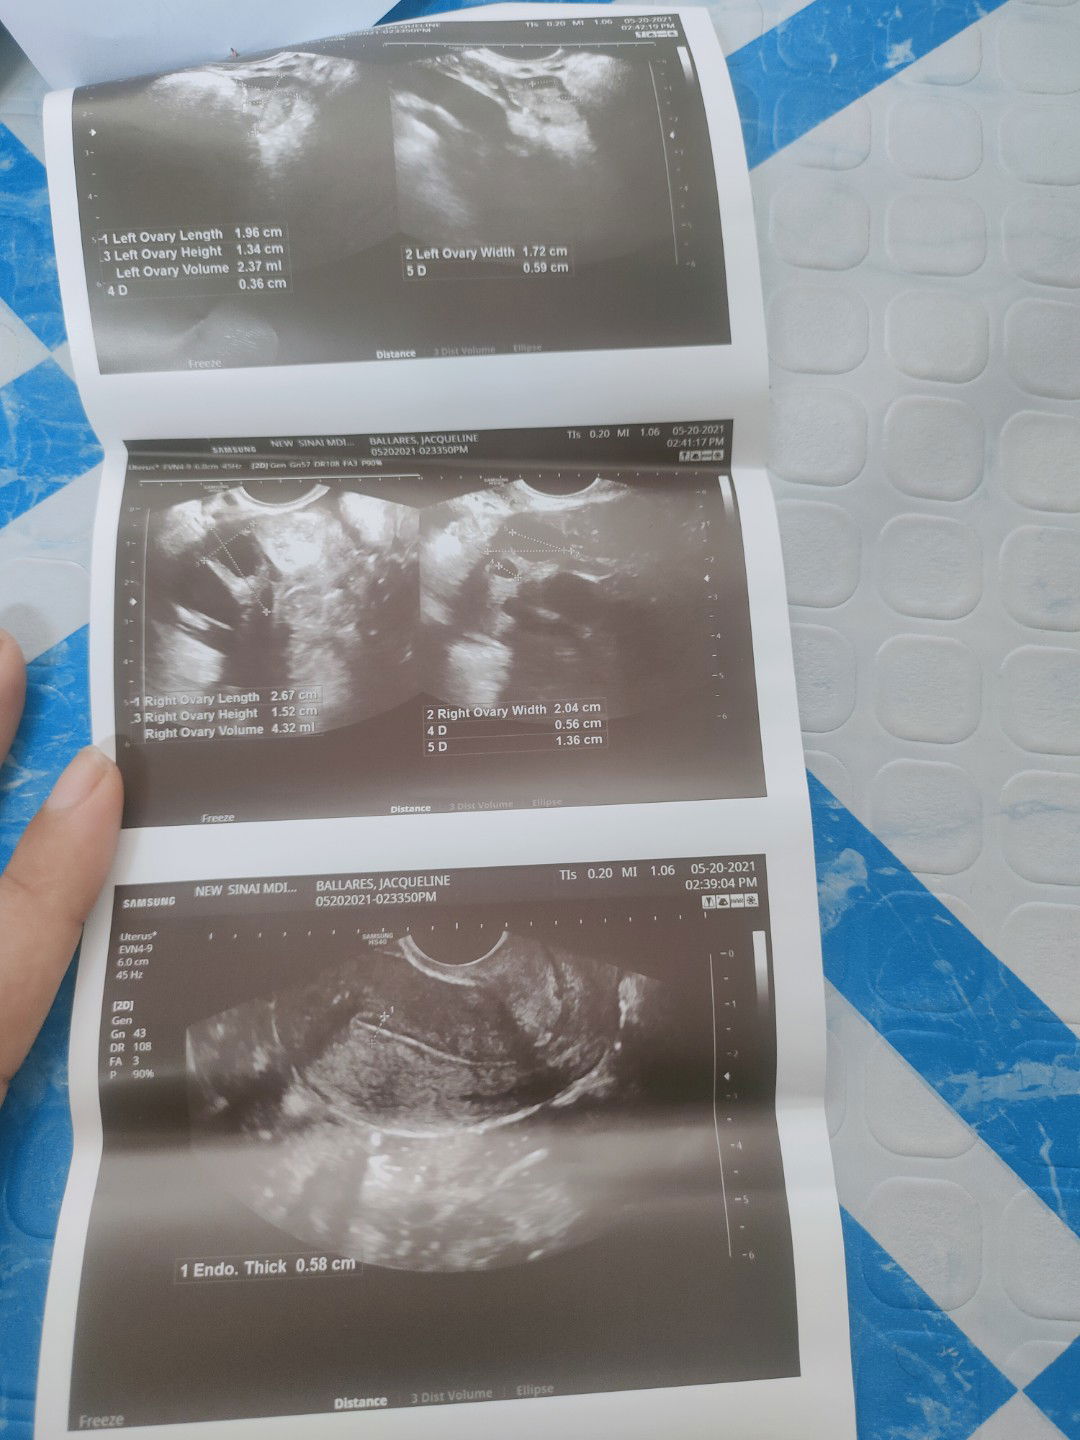

Done Check up..2 times na akong ngpatranvi.And for the second may follicle daw right Side Ng ovary .

ano daw ibig sabihin nyang follicle sa right side?